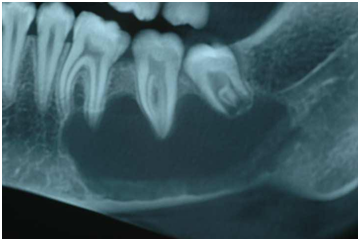

An asymptomatic, 16 years old Caucasian female was referred to a private office for evaluation of an impacted third molar located on the left mandible, with an unremarkable medical history. Intraoral and extra oral examination identified no signs of oral pathology. Panoramic radiograph revealed a unilocular radiolucency with clear margins extending within the molar area of the left mandible (Figure 1). The lesion was scalloping between the aforementioned teeth without any signs of root resorption, affecting the route of inferior alveolar nerve. The differential diagnosis included keratocystic odontogenic tumor, ameloblastoma and traumatic bone cyst. A surgical biopsy was suggested and the patient was operated under local anaesthesia. A mucoperiosteal flap was raised and under saline irrigation a bone window below the roots of 1st and 2nd molars was detached to expose the lesion (Figure 2). The bone cavity was completely empty of tissue or fluid without any epithelial lining while the inferior alveolar nerve was lying within it. The operative findings confirmed the diagnosis of TBC. Post operative course was uneventful with satisfactory bone healing on a follow-up panoramic radiograph.

Figure 1

Figure 2